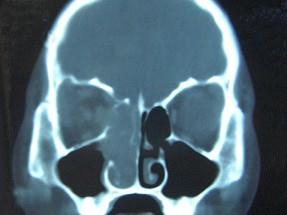

问题 女,16岁,鼻塞、流涕一年余,失去嗅觉,影像检查如图所示,最可能的诊断是 ( )

选项 A、小唾液腺癌 B、嗅神经母细胞瘤 C、筛窦癌 D、恶性淋巴瘤 E、鼻腔乳头状瘤

答案 B